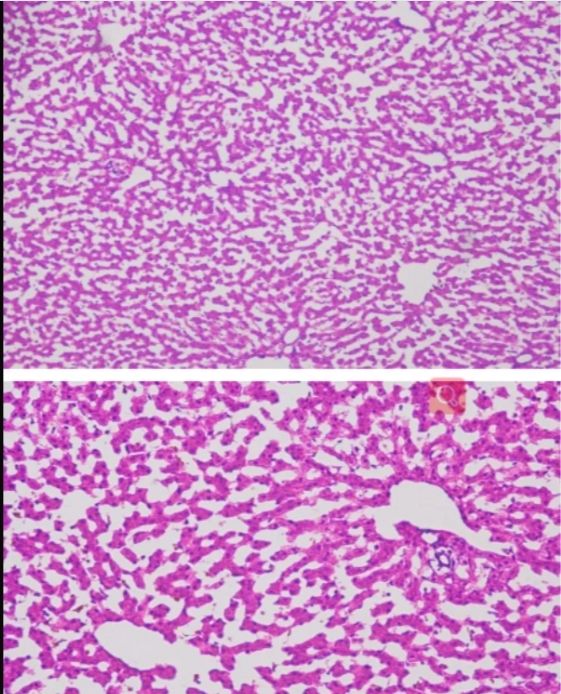

冰凍切片實(shí)驗(yàn)是生物學(xué)、醫(yī)學(xué)等領(lǐng)域中常用的一種實(shí)驗(yàn)技術(shù),主要用于觀察和研究生物組織的微觀結(jié)構(gòu)。在進(jìn)行冰凍切片實(shí)驗(yàn)時(shí),掌握一些關(guān)鍵的技巧對(duì)于獲得高質(zhì)量的切片至關(guān)重要。本文將詳細(xì)分享一些冰凍切片實(shí)驗(yàn)的技巧,幫助讀者更好地進(jìn)行實(shí)驗(yàn)。